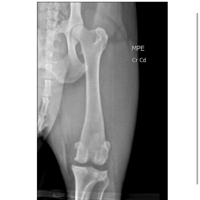

Olá pessoal me chamo Aline, e sou a dona do Blake um American bully de 3 anos que rompeu o ligamento das duas patas, onde é necessário uma cirurgia, o mesmo foi encaminhado a um hospital veterinário público, porém como a cirurgia é de grande porte e custo o governo não libera esse procedimento, sendo assim somente pode ser realizado em clínicas particulares, e eu no momento não tenho condições de arca com esse valor todo, quem puder estar ajudando com 1 real que seja já é de grande ajuda, vamos ajudar ele a fazer essa cirurgia e ficar bem, des de já agradeço a todos.